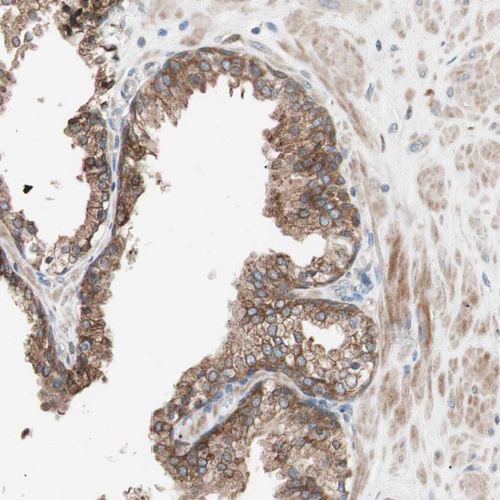

Immunohistochemical staining of human Prostate shows strong cytoplasmic positivity in glandular cells.